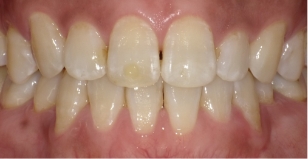

2025年夏、伊藤矯正歯科医院は抜歯を伴う矯正治療を行った症例の術後の安定度について統計的調査を行いました。その結果この症例のように、後戻りが最も現れやすいと言われる下の歯並びの前歯の部分で、他の矯正法に比べて大変に安定しているという結果が出ました。

これに対し伊藤矯正歯科医院では、抜歯を伴う矯正を行ったのちに何も装置を使用しなくて何年か経過しても、かなり安定している症例をみることが多くありました。(「安定調査症例1~4」と当HPの症例集ページ「叢生第3,4症例」をご覧下さい。)そこで治療が終わって数年経過した時点で、資料採得のできた14症例について歯並びの変化を観察しました。

これによると当院の治療後の歯並びの変化は、従来の矯正に比べ変化が非常に少ない事が分ります。つまり当院の矯正治療は、従来の矯正治療に比べ大変に安定していることが分かります。